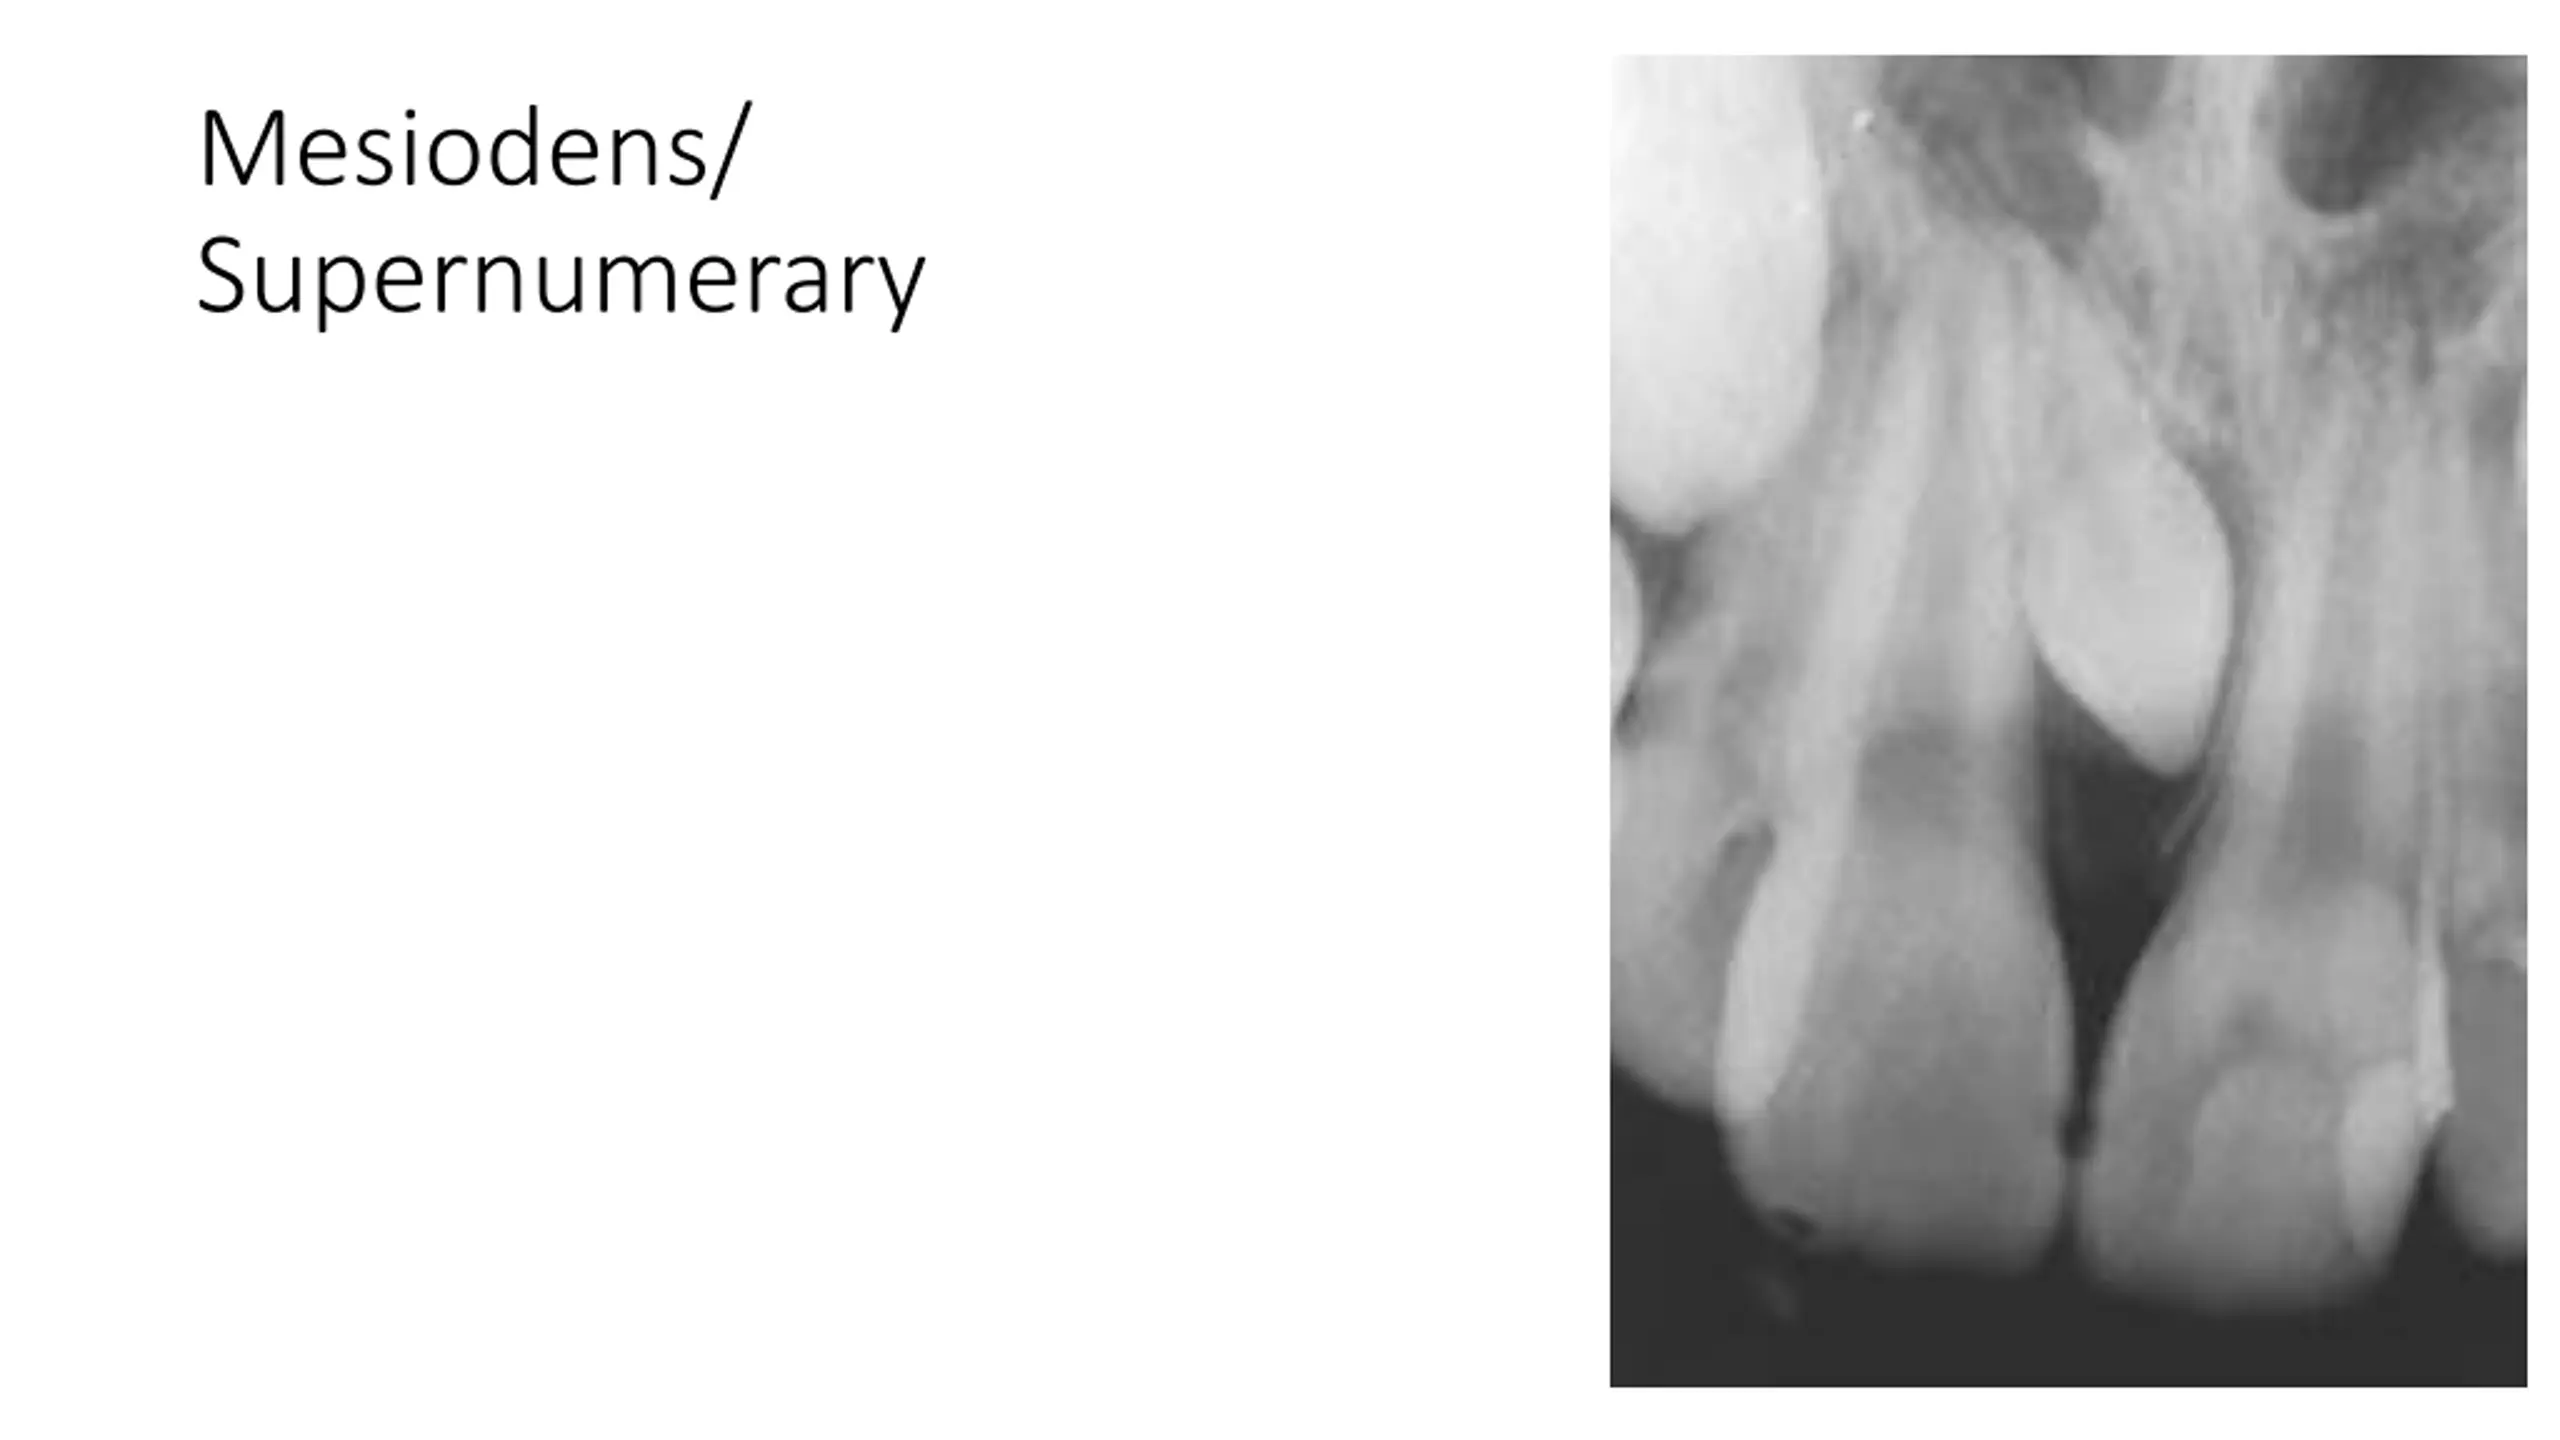

Mesiodens/ Supernumerary